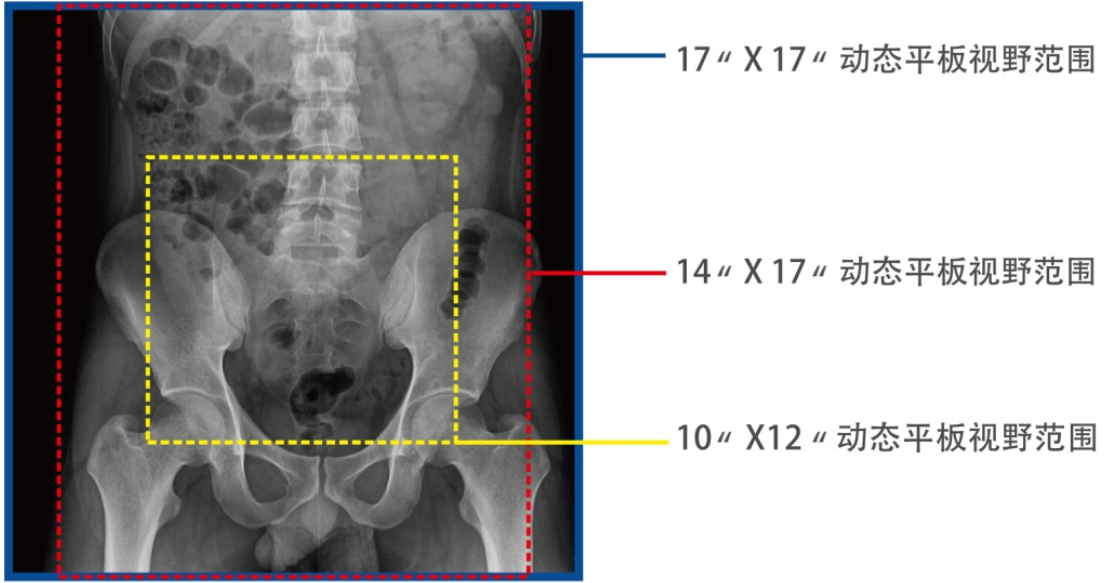

3、大尺寸平板探測器

1)能對患者的胸部腹部等部位實現大范圍全覆蓋,透視檢查無需對患者重新定位便可觀察到足夠大的人體器官組織,避免漏診誤診。